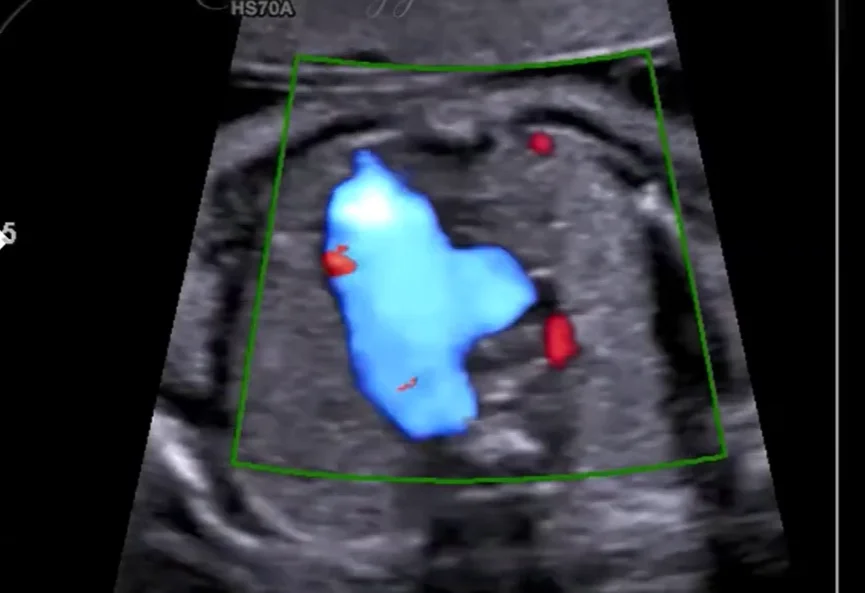

Phổi biệt trí thai nhi (Bronchopulmonary sequestration)

• Phổi biệt trí thai nhi (Bronchopulmonary sequestration)